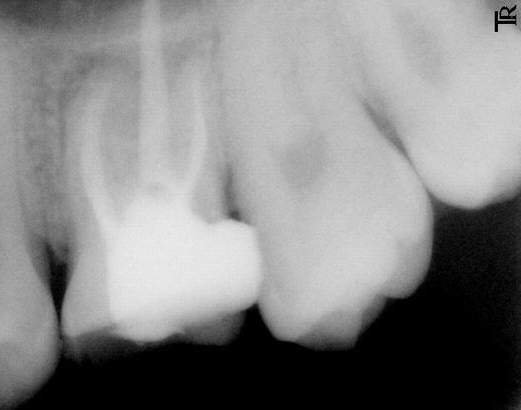

>>>>>>>>提问因为我的药都搞了三个月了都没搞好,人家说只要做根充就可能有好转的机会,可是一直都是在封药,结果落了个药物性根尖炎,还有,我估计医生没有给我做根充,因为我去拍过片子了,没有发现那几根白色的根(

/art_img/200708/19_0133432466.jpg;这张是别人的,做过根管治疗的),而我的没有,很正常的根,不是白色的。现在三个月了,还是疼,特别是外刷时,但很奇怪,最近去换药时,不管他怎么用力去撬都不疼的,但如果深入地去捻的话就会很痛很痛哩,现在他给我封的药是fc+碘,不明白为什么。。。

>>>>>>>>休闲养生网回答:拍摄X线片,根管内没有白色的充填物,可以肯定根本没有根管充填.与根管封药相比根管充填相对要麻烦一点,需要将半固体的药剂和固态的牙胶尖一起充填到根管内.要充填合适不能欠充或超充,欠充容易导致以后根尖炎的复发,超充会刺激根尖组织,导致疼痛感染.所以一定要在X线的指导下进行根管充填,做到恰到好处.